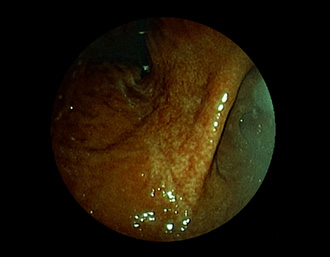

胃潰瘍(Stage S1)・・治療後5ヶ月

潰瘍の中心に白苔はなく、わずかに陥凹する潰瘍面に発赤が残る再生上皮が覆い尽くす(赤色瘢痕)。集中皺襞がなだらかに中心に延びている。→ ヘリコバクター・ピロリ感染を認めたため、除菌治療で駆除しました。

(通常画像)